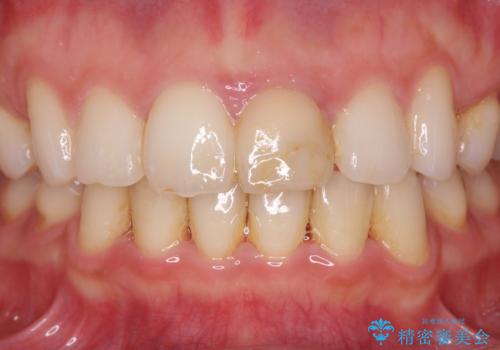

根管治療は行わず、仮歯・ジルコニアクラウンのみの処置を行い自然な歯に仕上げることができました。